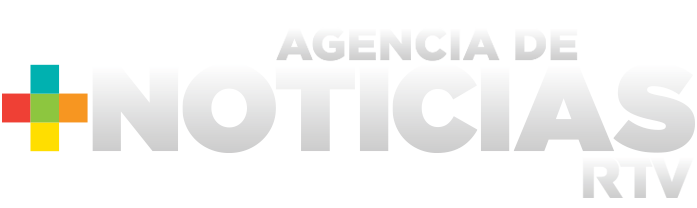

La saliva, excelente barrera de defensa para el cuerpo: Isaac Cerda

Agencias de Noticias RTV (UV), 14 de julio de 2020